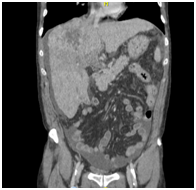

A CT angiography of the chest was performed, and a bilateral PE was found (Figure 1A). Anticoagulant therapy with low-molecular weight heparin was administered (1mg/kg, q12h). The CT angiography also revealed a liver mass and a CT of the abdomen was performed.

Figure 1 CT scanning. (A) Chest enhanced CT showing PE (arrow). (B) Enhanced CT of the abdominal region showing a large low-density lesion, sized 11.5x9.7 cm, in the right lobe (arrow). (C) Enhanced CT of the abdominal region showing tumour thrombus invasion of the IVC and RA (arrow). (D) Coronal reconstruction showing tumour thrombus invasion of the IVC and RA (arrow).

The CT revealed parenchymal heterogeneity of the liver, suggesting cirrhosis, and a sizeable lesion (11.5 x 9.7 cm) in the right lobe (Figure 1B). The lesion showed typical HCC image pattern, with an arterial phase enhancement and a venous/delayed phase washout. A hyperattenuating material in the portal vein (PV) lumen was also found, with no enhancement after contrast injection, inferring thrombotic/tumoral process; and a hyperattenuation in the IVC was also described (Figure 1C&D). Transthoracic echocardiogram confirmed tumoral invasion of the vena cava and right atrium.